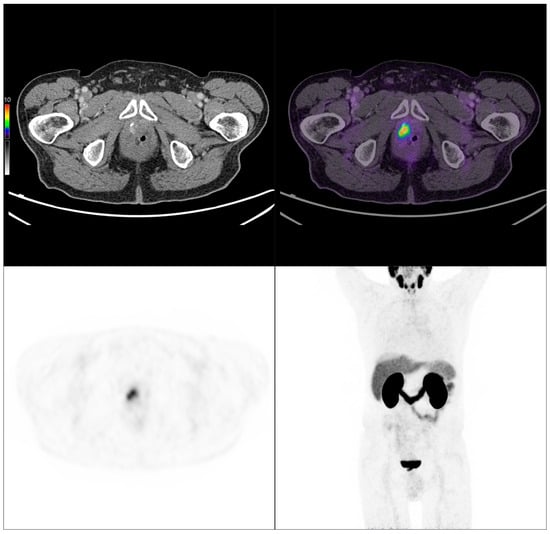

PSMA PET/CT scan of an 84-year-old patient with biochemical recurrence (PSA: 0.67 ng/mL). Initially, the Gleason score was 4 + 3 = 7, pT3 pN0 M0, and treated with radical prostatectomy. Imaging performed following intravenous administration of 141 MBq of [68Ga]Ga-PSMA-11 revealed a local recurrence.

Figure 8.